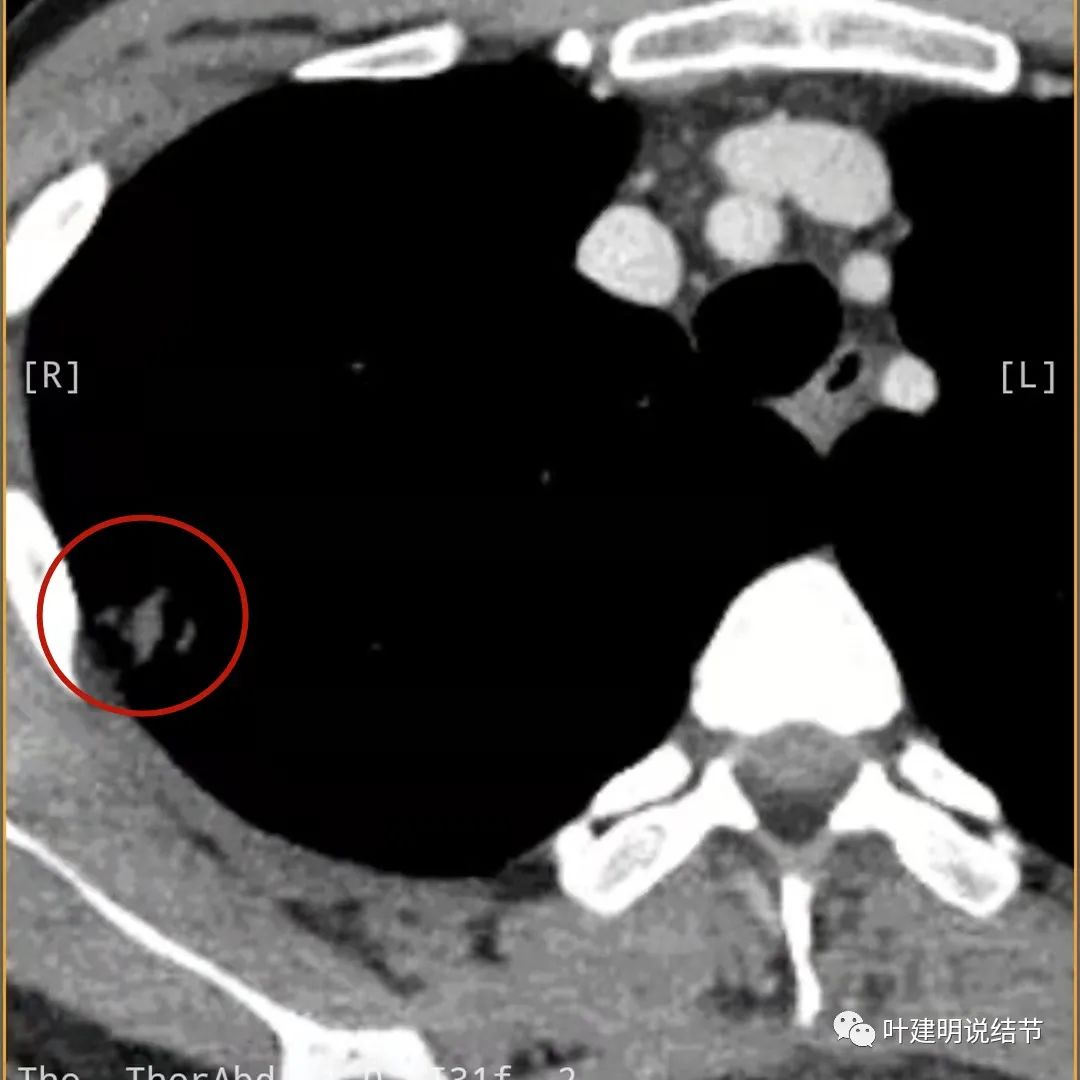

上面是她提供的病史资料,其中最重要的是PPD强阳性!其他主要看影像,我们先来看她2020年7月份的平扫片子(由于片子较多,详细展示是为了同道分析,我在影像特征描述上将只选取部分加以说明):

右肺尖偏实性结节(粉色箭头),邻近胸胸膜明显增厚不平,且广基附在胸壁上(蓝色箭头)